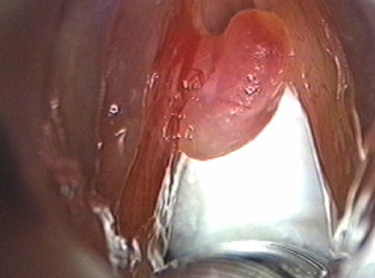

성대폴립은 성대결절과 같이 음성남용에 의한 2차 손상에 의하나,

상기도 감염 등으로 성대 점막의 superficial lamina propria의

미세 혈관구조에 외상이 발생하여 생긴 질환입니다.

쉰목소리이며 폴립의 크기와 위치에 따라 증상의 변화가 다양하게 나타납니다.

범발성인 경우에는 증상이 심하며 호흡곤란도 일어날 수 있으며 후두검사상 국한적인 경우에는 주로 일측성성대에 국한 되어 나타납니다.

후두미세수술로 제거하거나 PDL레이저성대수술을 이용하여 제거하며, 목소리의 남용이 원인일 때는 음성치료를 병행하는 것이 좋습니다.